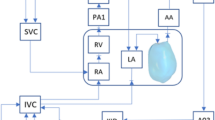

For patient-specific FE simulation of both pre-FAV and post-FAV LVs, 3D reconstructions of the LV myocardium, left atrium (LA) cavity and right ventricle (RV) cavity were first performed as previously reported (Green et al. 2022). Briefly, 2D slices were extracted from the 4D volume files, and then, binary segmentation of the myocardium was performed using a lazy snap algorithm (Li et al. 2004). 3D reconstruction was then performed with VMTK (www.vmtk.org), with the reconstructed geometries smoothed in Geomagic (Geomagic Inc., Morrisville, NC, USA). 3D motions of the LV, LA and RV were extracted using a validated cardiac motion estimation algorithm (Wiputra et al. 2020). The algorithm modeled motion in the image with spatial b-splines of temporal Fouriers, and was curve-fitted to the displacement fields from 3D pair-wise registration images of consecutive time points. The final reconstructed LV geometries are depicted in Fig. 1, where satisfactory tracking can be demonstrated in Supplementary Fig. S1.

2.4 FE and lumped parameter modeling formulation

Image-based, patient-specific FE modeling of fetal LV myocardial biomechanics was performed in accordance with our previous methodologies (Green et al. 2022; Ong et al. 2020), where the FE model was connected to a lumped parameter model to enable ventricular-vascular coupling (Pennati et al. 1997; Pennati and Fumero 2000). The lumped parameter model used was based on Pennati et al.’s work (Pennati et al. 1997; Pennati and Fumero 2000) and was age scalable to a range of gestational ages, through a series of allometric equations. The model underwent minor recalibration using descending aorta pulse pressure measurements (Versmold et al. 1981) and more recent measurements of human fetal intracardiac pressure (Johnson et al. 2000), further details have been supplied in Supplementary Material Section 3.0. Our FE and lumped parameter codes have been made available at https://github.com/WeiXuanChan/heartFEM.

where LA capacitance was assumed based on the gestational age-specific value derived in the lumped parameter model (Pennati et al. 1997; Pennati and Fumero 2000). LV myocardium models, displayed in Fig. 1, were meshed with a minimum of 2500 quadratic tetrahedral elements, which was sufficient for mesh convergence as shown in our previous study (Ong et al. 2020). The formal FE simulation was performed by minimizing the weak formulation of a Lagrangian function described by Shavik et al., which enforced tissue stress equilibrium, incompressibility, and required a specific cavity volume to yield cavity pressure, using the Newton Solver in the FEniCS software (Shavik et al. 2018). The boundary conditions were like that previously reported (Shavik et al. 2018), with the basal plane of the LV constrained in the longitudinal direction and a weak 90 Pa spring applied to the entire epicardium at the load-free state, to constrain translational motion of the model and to imitate the behavior of the surrounding tissues. The model was executed for 30 cycles, to ensure steady state was achieved.

During the patient-specific matching optimizations, a gradient descent algorithm was used to optimize the Doppler gradients for MV, MVr and AV, to simulated pressure gradients, while another gradient descent algorithm was used to optimize the match between simulated and imaged stroke volume (Fig. 2). The solution was deemed convergent if errors for all parameters were < 10%. If this was not achieved, the age scaling of the lumped parameter model was adjusted, and the iterative matching process repeated. This age scaling adjustment represented a way to adjust for fetal body size variability or body developmental maturity.